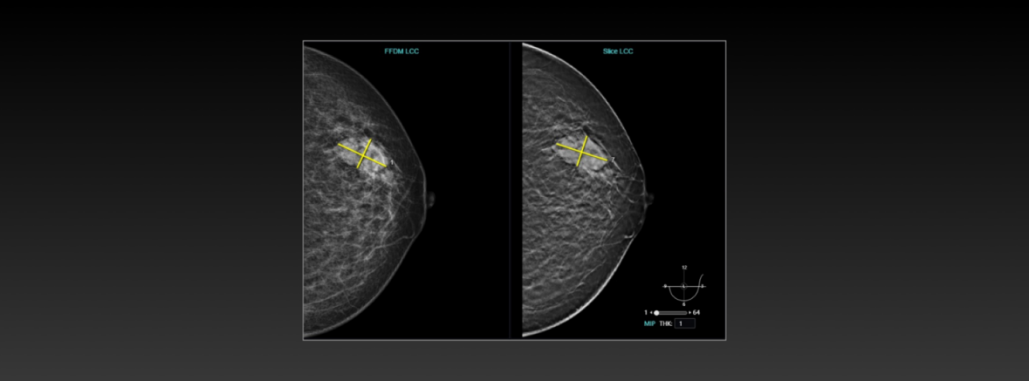

联影智能DBT乳腺AI人工智能分析系统

联影智能DBT乳腺AI人工智能分析系统,能够辅助医生评估乳腺腺体密度类型及乳房内病灶的检出。该DBT乳腺AI人工智能分析系统全方位贴近医生阅片流程,可以提升医生的阅片和工作效率,降低乳腺癌漏诊率,助力两癌筛查。

DBT乳腺AI人工智能分析系统能够实现智能检出与量化分析

联影智能DBT乳腺AI人工智能分析系统曾辅助检出过患者右乳外上象限上连续多层存在肿块伴钙化,并提示医生该处需追加进行乳腺对比增强检查。

令医生印象深刻的是,追加检查的MR乳腺平扫+增强_1.5T高压结果证实了该DBT乳腺AI人工智能分析系统的判断准确,考虑此处病灶为退化型纤维腺瘤。DBT乳腺AI人工智能分析系统助力放射科进行乳腺癌精准筛查和诊断的临床价值得到验证。